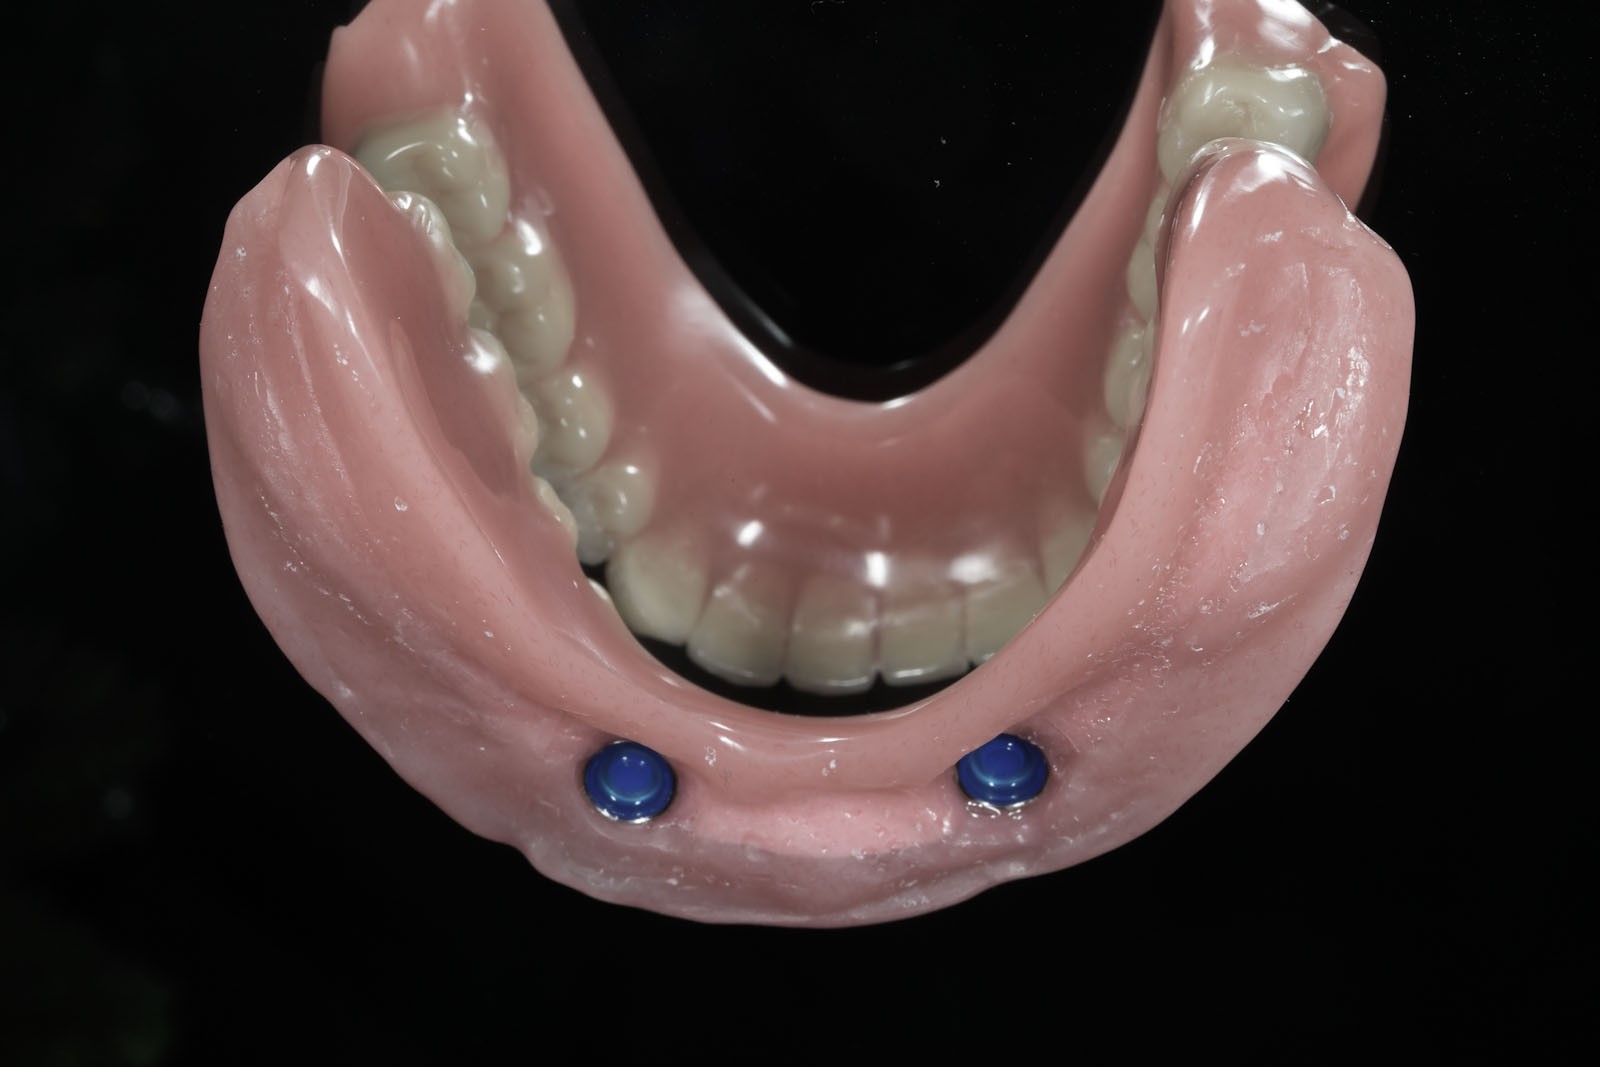

Protezy Overdenture, czyli nakładowe

Są pośrednim rozwiązaniem pomiędzy ruchomymi protezami osiadającymi a na stałe montowanymi na implantach mostami. To również ruchome protezy o zredukowanej płycie, których zasada działania polega na tym, że są częściowo wsparte na implantach.

Zazwyczaj umocowuje je do podłoża od 2 do 4 wszczepionych implantów, dla których optymalną pozycją jest przednia część wyrostka zębodołowego szczęk lub żuchwy.

Za stabilizację pomiędzy płytą protezy nakładowej a wszczepami odpowiedzialne są różnego typu odpowiadające sobie elementy retencyjne. Z jednej strony przytwierdzone są do szyjek implantów, z drugiej – do płyty protezy Overdenture.

Ze względu na rodzaj zastosowanych elementów zaczepowych istnieje kilka sposobów stabilizacji protez na implantach:

Protezy Overdenture (nakładowe) to ruchome uzupełnienia protetyczne, które dla podparcia i stabilizacji w jamie ustnej wykorzystują wszczepione uprzednio implanty. Niezbędna do prawidłowej konstrukcji takiej protezy ilość implantów to 2–4. Zaletą protez Overdenture jest niewątpliwie możliwość redukcji płyty protezy i lepsza jej stabilizacja dzięki elementom retencyjnym przytwierdzonym z jednej strony do implantu, a z drugiej do płyty protezy. Ze względu na rodzaj zastosowanych w nich elementów retencyjnych wyróżnia się zespolenia typu locator, kulkowe, belki Doldera, połączenia teleskopowe, magnesy i mieszane (różne zespolenia).

Ważnymi aspektami zastosowania protez Overdenture jest ich dobra stabilizacja w porównaniu z protezami całkowitymi zakładanymi do jamy ustnej bez wszczepiania implantów oraz zahamowanie procesu resorpcji kości i wyrostka zębodołowego.